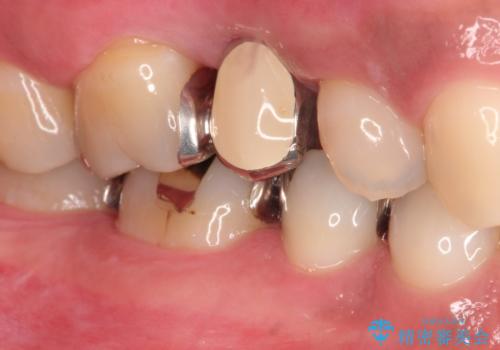

右上のブリッジが途中で切断されて、手前の歯が根の治療の途中でした。

根の治療を行いその後にオールセラミックブリッジを装着する計画となりました。